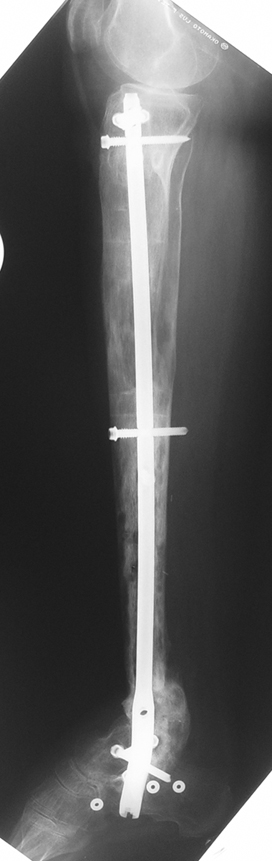

Pseudarthrosis of fracture and pseudarthrosis treatment is currently important problem for orthopedic surgery. Various treatment modalities have been described for pseudarthrosis treatment. All of the treatment methods include high complication rates and additional problems. Leg-length discrepancy, deformity and soft-tissue loss and chronic infection can concomitance with pseudarthrosis. Many internal or external fixation techniques have been described for pseudarthrosis.

Debridement and resection of bone fragment from the pseudarhtosis area vascularized or nonvascularized fibula graft, vascularized muscle flaps, bone grafting followed internal fixation techniques make a option for treatment of pseudarthrosis treatment. But these treatment modalities may not correct deformity and leg-length discrepancy.

Recently, ilizarov techniques which is basis depend on distraction osteogenesis , bone segment transport or acute shortening after the resection at the site of pseudarthrosis combined with lengthening at another level of bone have been used. These treatment techniques may include some advantage for problems of infection, leg-length discrepancy, soft-tissue loss, and joint contracture.